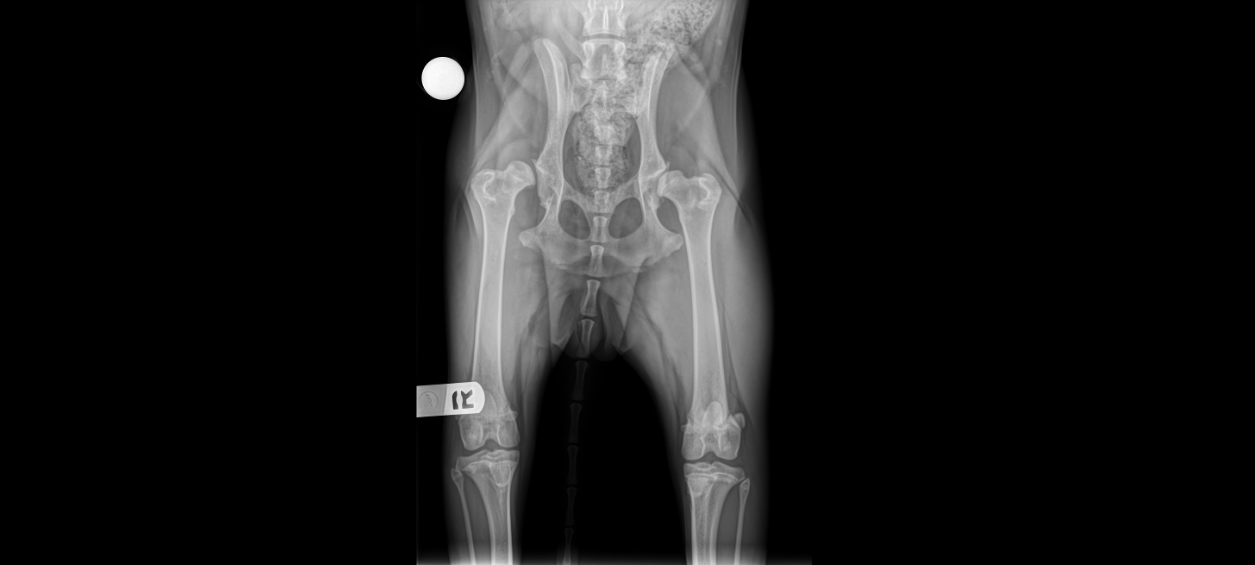

From www.neamc.com

Total Hip Replacement (THR) Surgery New England Animal Medical Center Total Hip Replacement Surgery Anesthesia Choosing the correct multimodal analgesic regimen (mma) in patients undergoing tha is of utmost importance, as this can. Multimodal analgesia seems to play a major role in the perioperative care of patients undergoing total hip arthroplasty (tha). Total hip replacement can be performed under general, spinal or epidural anaesthesia, and often a combination of. Spinal or general anaesthesia is recommended.. Total Hip Replacement Surgery Anesthesia.

Total Hip Replacement (THR) Surgery New England Animal Medical Center Total Hip Replacement Surgery Anesthesia Choosing the correct multimodal analgesic regimen (mma) in patients undergoing tha is of utmost importance, as this can. Regional anesthesia is a safe and effective technique that allows you to avoid general anesthesia. Multimodal analgesia seems to play a major role in the perioperative care of patients undergoing total hip arthroplasty (tha). Total hip replacement can be performed under general,. Total Hip Replacement Surgery Anesthesia.